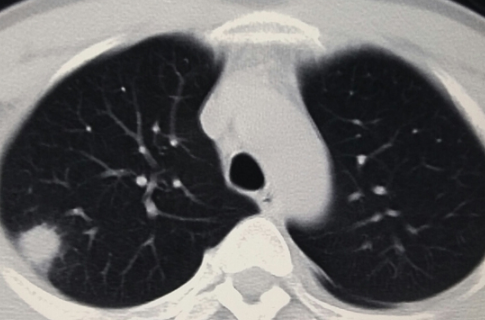

这种说法是不准确的。有些肺结节比较小,没有症状,可以定期复查。若肺结节较大,需进一步完善支气管镜及CT引导下经皮肺穿刺,明确结节性质。

但是X线对软组织的分辨率不是很高,小于一厘米的结节很难发现。现在,越来越多的人在体检时选择胸部CT检查。这样,随着医学影像诊断技术的进步,两到三毫米的肺结节也能被发现和检测到。因此,总的来说,肺结节的发现率越来越高。

正常人群肺结节检出率因地区而异。根据目前的情况,最低可能是20%,最高可能是40%-50%,甚至70%,这可能与参与调查的正常人群有所不同。年龄不一样。 30-70岁的正常人可能会发现70%的人有肺结节,一般在20%-40%左右。肺结节发生率高,但恶性程度低。有可能90%以上的肺结节是良性结节,最终诊断为恶性肿瘤的约有5%左右。

肺结节的发病率虽然高,但主要是由非肿瘤因素引起的。由于肺癌是最常见的癌症,大家对肺癌的关注度也越来越高。肺癌的监测和筛查方法通常是胸部CT。胸部CT做的越多,肺结节的发生率和检出率就会增加。由于肺癌仅占其中的5%左右,因此肺结节大可不必过于紧张。 .必要的检查、观察和随访更为重要。做到早筛查、早发现、早治疗。大多数肺癌患者都能取得较好的治疗效果。